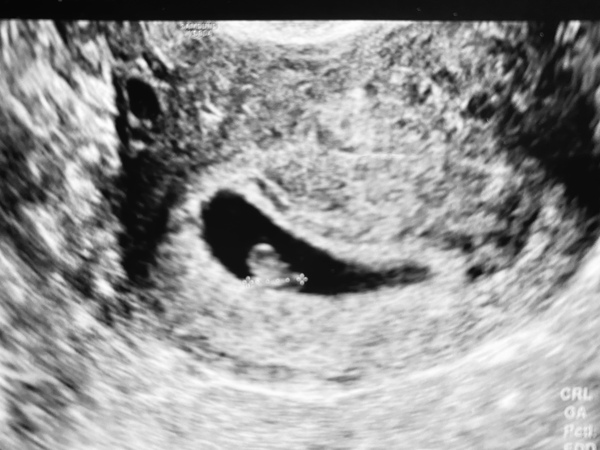

By the way - I had my ultrasound last night (at 6 weeks +6). Apparently all is good! DH and I heard and saw the little heart, it was surreal! 🥰 My GC measured little baby at 6 weeks + 3-5 days, so that triggered alarm bells again. But she said not to worry as it's so difficult to measure and we're just talking about 1 mm. Still... the doubt remains. Why are we so tough on ourselves and have to worry like crazy. Don't get me wrong, I'm SUPER happy but still worried about anything that can go wrong.

Hi @goldencloud, what a lovely picture, can't wait to add mine to the collection on Thursday :) It's great you heard the heartbeat as well, I think I will be happy even if they say it's not an ectopic and nothing else. I do believe same way as us we are not all the same height/weight so I don't think you should worry about those couple of days difference in measurement either.

@GoldenCloud, lovely to see another scan pic, it had been a week or so. Congratulations on seeing the heartbeat! I got no measurement or dating at my scan, it was a fairly crap experience, and was worried about size really ever since. But I'm nearly three weeks later and still no bleeding or anything, so I think you just have to trust that if there is a problem, they will know. For now you have no reason not to trust them that it's all fine :)

Lovely scan pic there @GoldenCloud

@GoldenCloud lovely picture! I wouldn't worry about 3 days plus/minus. Our doctor also said it's hard to measure at this early stage.

Hi guys sorry for late update just been caught up with so many things happening right now . But the scan definitely brightened up our day it was perfect healthy baby measuring 8 weeks . Shame our clinic didn't do heartbeat sound so we only manage to see it 💗 and not hear .

Basically the nurse was running late and a 20 min appointment was done in very quick 10 mins she was in so much rush I was very annoyed my dh had to ask her to take video she was hesitant but then allowed and she forgot to grab pics 😏. But we managed to see the baby and flicker so to be positive and moving forward .. with EDD 12 October ( which is what i calculated so bang on so far ) another countdown for 12 week scan on 31 at March .. cannot wait that long 😜